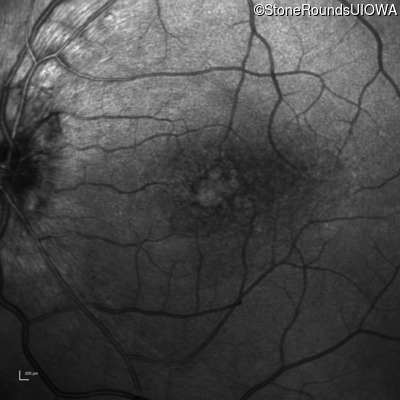

Infrared Fundus Photograph - Right - 20/30 -2

Exemplar